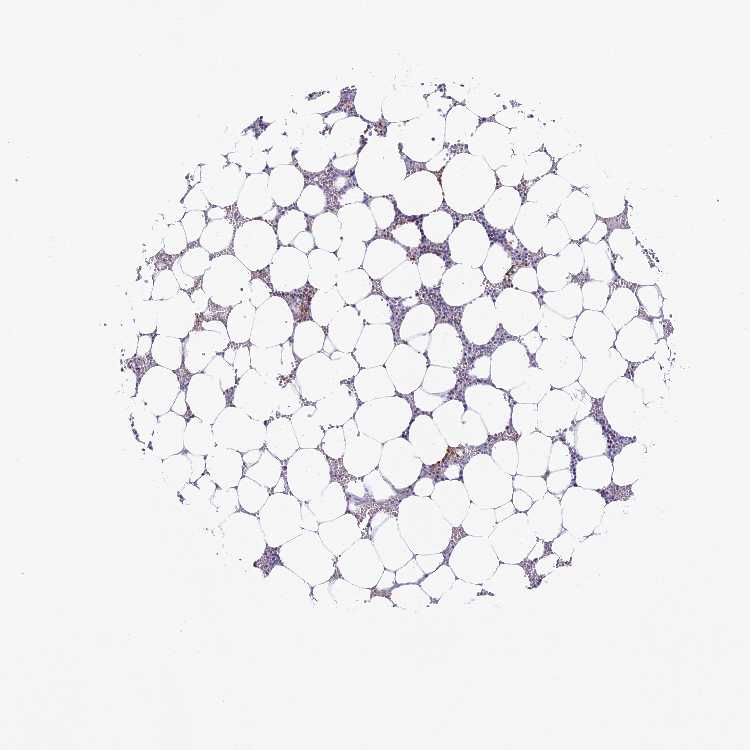

BONE MARROW - Antibody stainingi

Antibody staining in the annotated cell types in the current human tissue is reported as not detected, low, medium, or high, based on conventional immunohistochemistry profiling in selected tissues. This score is based on the combination of the staining intensity and fraction of stained cells.

Each image is clickable and will lead to virtual microscopy that enables deeper exploration of all samples and also displays staining intensity scores, fraction scores and subcellular localization as well as patient and tissue information for each sample.

Antibody HPA043998

Hematopoietic cells Not detected